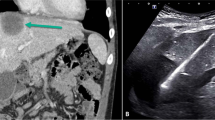

Irreversible electroporation (IRE) is a promising IO technique where two to six probes are placed percutaneously into a tumor, which is then shocked by high-voltage microsecond electrical pulses. This technique causes tumor cell apoptosis (progression to irreversible cell death) by having the electrical pulse cause permanent pores in the tumor cell membrane [5]. Reversible electroporation was first described in 1984 [6] and has been used for many purposes, including transfecting viruses into cells for gene therapy [7]. When IRE was recently demonstrated on a porcine liver, the target liver tissue underwent apoptosis, but supporting structures within the ablation zone, such as blood vessels and bile ducts, were spared [8]. The first Phase I study was of renal cell carcinoma treated with IRE immediately before resection. The technique was found to be safe with no major complications [9]. The advantages of this nonthermal ablation technique in pediatric tumor ablation compared to radiofrequency ablation include no grounding pads necessary thus avoiding possible skin burns [10]; no heating occurs avoiding hyperthermia during ablation of large tumors in small children [11]; the procedure is quick avoiding long anesthesia times, and the ablation zone is immediately delineated as a hypoechoic area by ultrasound [8]. A single bipolar probe (NanoKnife, www.Angiodynamics.com, Angiodynamics, Queensbury, N.Y.) is being developed for clinical use.